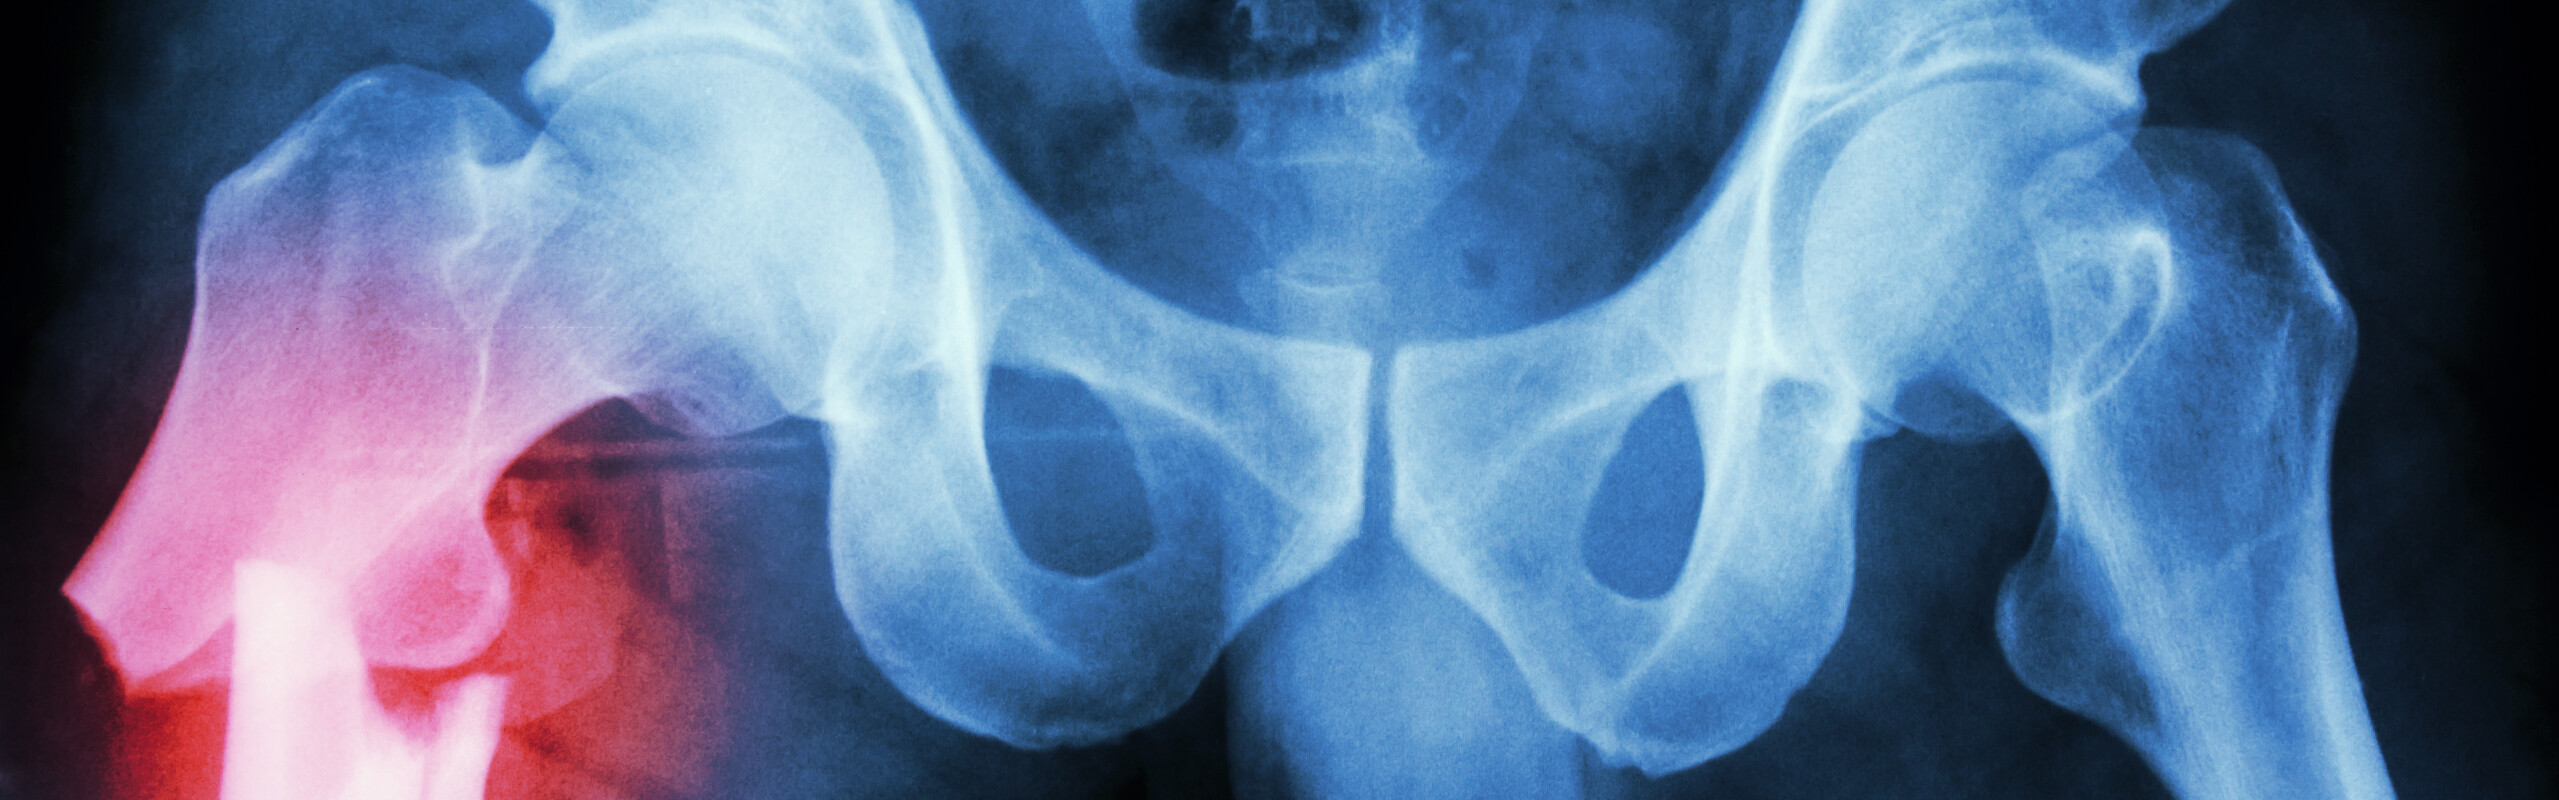

Höftfraktur och depression – finns ett samband?

REPORTAGE Hur påverkas äldre personer som opereras för höftfraktur när det gäller smärta, funktion, depression och risk för ökad dödlighet? Om detta forskar Erika Olofsson, doktorand på Institutionen för omvårdnad.

En annan studie handlar om ifall operationsmetod har betydelse för smärta och funktion efter en inte felställd höftfraktur, det vill säga då brottytorna inte har glidit isär. Det är två kirurgiska metoder som jämförs – en då brottet spikas ihop och en då höftprotes sätts in.